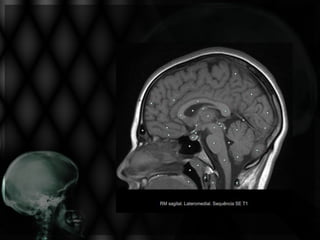

AVE ISQUÊMICO NA RM

À RM o sinal depende

da fase pós-AVE.